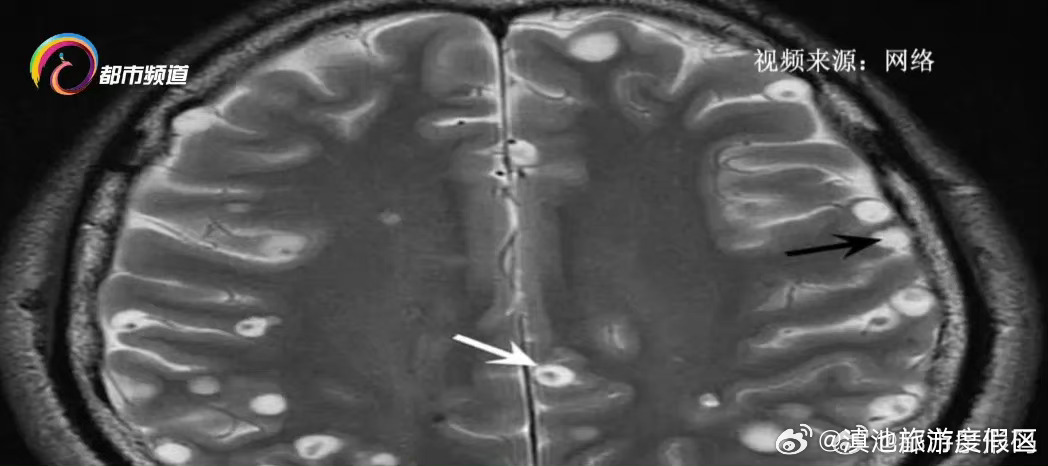

在云南部分地区有食用生食的饮食习惯,不少人喜欢吃生腌、鱼生等食物。医生提醒,这些食物虽鲜嫩、开胃,但有感染寄生虫的隐患→(@都市条形码)

男子头痛,检查发现脑里有一圈一圈的东西!真相细思极恐,很多人爱吃……